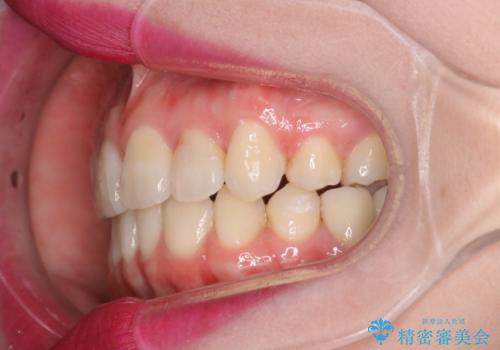

八重歯のワイヤーによる抜歯矯正 矯正治療と並行してセラミック治療も

- 八重歯と前歯のガタガタを主訴に来院されました。

左下の奥歯がすでに1本抜歯されており、ブリッジを装着されていました。

ブリッジを除去して、左下以外の上顎両側と右下の歯を合計3本抜歯して矯正する計画としました。